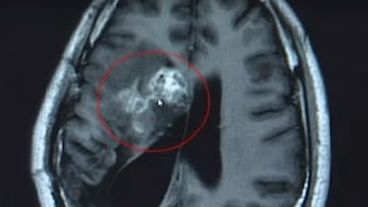

Un chino fue operado a finales del pasado mes en un centro médico de la provincia de Guangdong, donde le extirparon de su cerebro un parásito vivo de doce centímetros de largo. El gusano se alimentó de sus tejidos durante quince años. Aparentemente, todo se inició por comer caracoles que no estaban bien cocidos.

Según publicó Russia Today, el neurocirujano Gu Youming, quien dirigió la operación que duró más de dos horas, explicó que si no extraían el parásito, la tenia habría seguido comiendo la masa cerebral del hombre, lo que podría haber producido parálisis o la muerte.